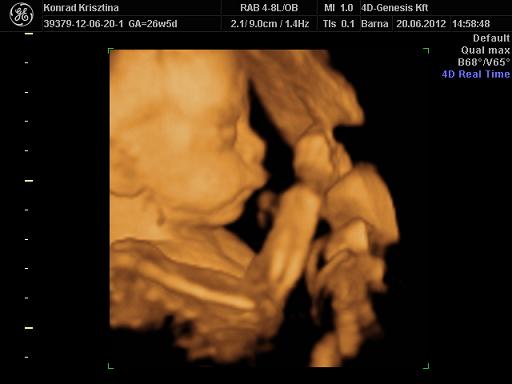

Rizsmike: eszméletlen jó minőségű UH képek :)